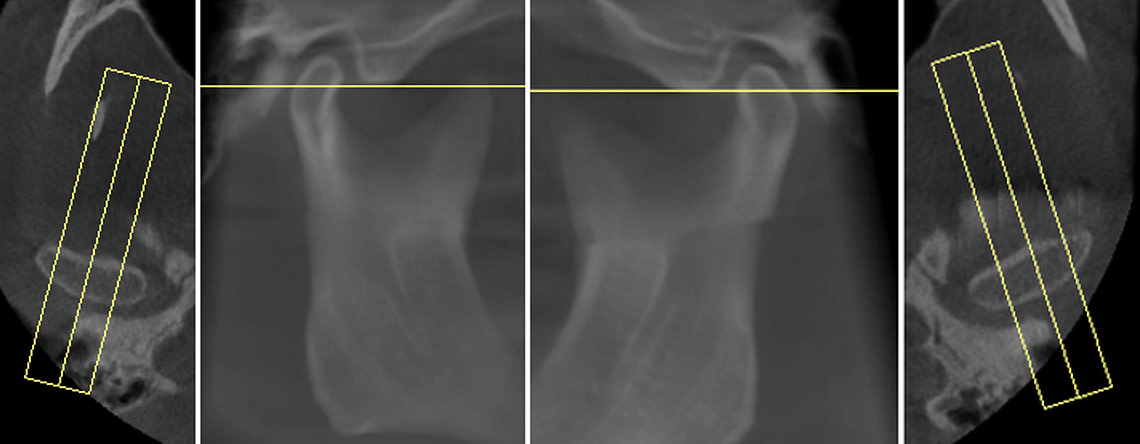

Tooth number is selected to analyze the root canal morphology within the CBCT radiograph.

Sagittal and coronal slices and highlighting the angle/curvature/length of the canals.

Measurement of periapical radiolucency volume is a unique advantage with 3D CBCT versus 2D PA. These are endodontic reports for tooth 12 which had a very large periapical radiolucency. The reports were done before and after a long-term calcium hydroxide dressing.

The endodontic report could provide a better visualization of the shape of the root canals in 3 dimensions. It would be helpful to calculate the curvature angle to estimate the root canal's difficulty. Working length measurements of canals are shown automatically but measured from the pulpal floor. Typically, clinicians would estimate the working length of the radiograph by measuring from a common reference point such as the cusp tip or incisal edge.